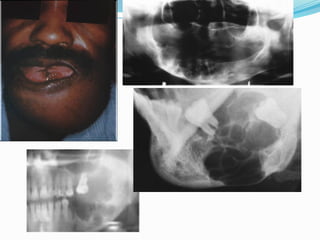

 It may arise from the lining of a

dentigerous cyst but more often

arises independently of

impacted teeth. It is

characterized by a progressive

growth rate and , when

untreated, may reach enormous

proportions.

 Early symptoms are often

absent, but late symptoms may

include a painless swelling,

loose teeth, malocclusion, or

nasal obstruction

Maxillary tumors frequently

perforate into the antrum and may

grow freely, with extension into the

nasal cavity, ethmoid sinuses, and

skull base.

 Ameloblastomas of this type arising in the maxilla are

particularly dangerous as it is often difficult in getting

adequate margins.